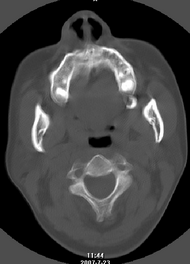

以下是引用还珠格格在2007-7-31 19:32:00的发言:[br]右侧鼻前庭内可见软组织块影,部分鼻中隔包绕其内,邻近骨质未见明显吸收破坏,考虑 1、鼻息肉可能性大 内翻乳头状廇不除外。期待结果。

以下是引用zjzjr在2007-7-31 20:29:00的发言:[br]右侧鼻前庭内可见软组织块影,部分鼻中隔包绕其内,邻近骨质未见明显吸收破坏,考虑 1、鼻息肉可能性大 内翻乳头状廇及肉芽肿类病变除外。期待结果。